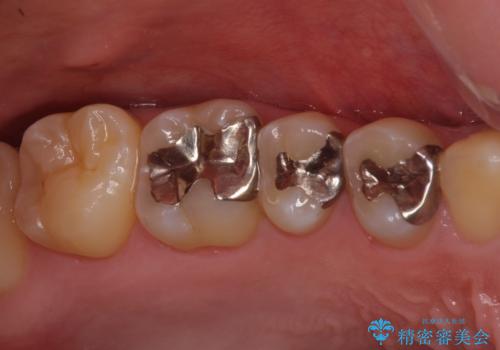

銀歯を白くしたい セラミックによる審美歯科治療

- 治療中の前歯と口腔内にある銀歯が気になるとのことで来院された患者様です。

土台に含まれている金属も含め、口腔内の金属は全て除去し、根管治療が必要な歯は根管治療を行い、オールセラミッククラウンやセラミックインレーにて治療することとしました。